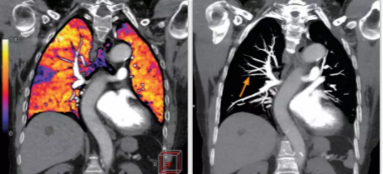

相比傳統(tǒng)成像方式,肺部柔性減影技術(shù)通過人工智能,對平掃數(shù)據(jù)和CT肺動(dòng)脈血管掃描數(shù)據(jù)進(jìn)行智能比對,解碼并識(shí)別各個(gè)器官(肺、氣管、肺動(dòng)脈、肺靜脈、主動(dòng)脈等)的空間位置,并在三維空間中進(jìn)行體素級的柔性配準(zhǔn),從而極大提升了不同序列數(shù)據(jù)的空間位置的一致性。通過肺部柔性減影技術(shù)可得到肺強(qiáng)化碘圖,可以顯示出傳統(tǒng)CTPA圖像看不到的小栓塞病變,提高了栓塞檢出率,其結(jié)果甚至可與SPECT吻合。

肺智能柔性減影成像功能發(fā)現(xiàn)亞段肺栓塞